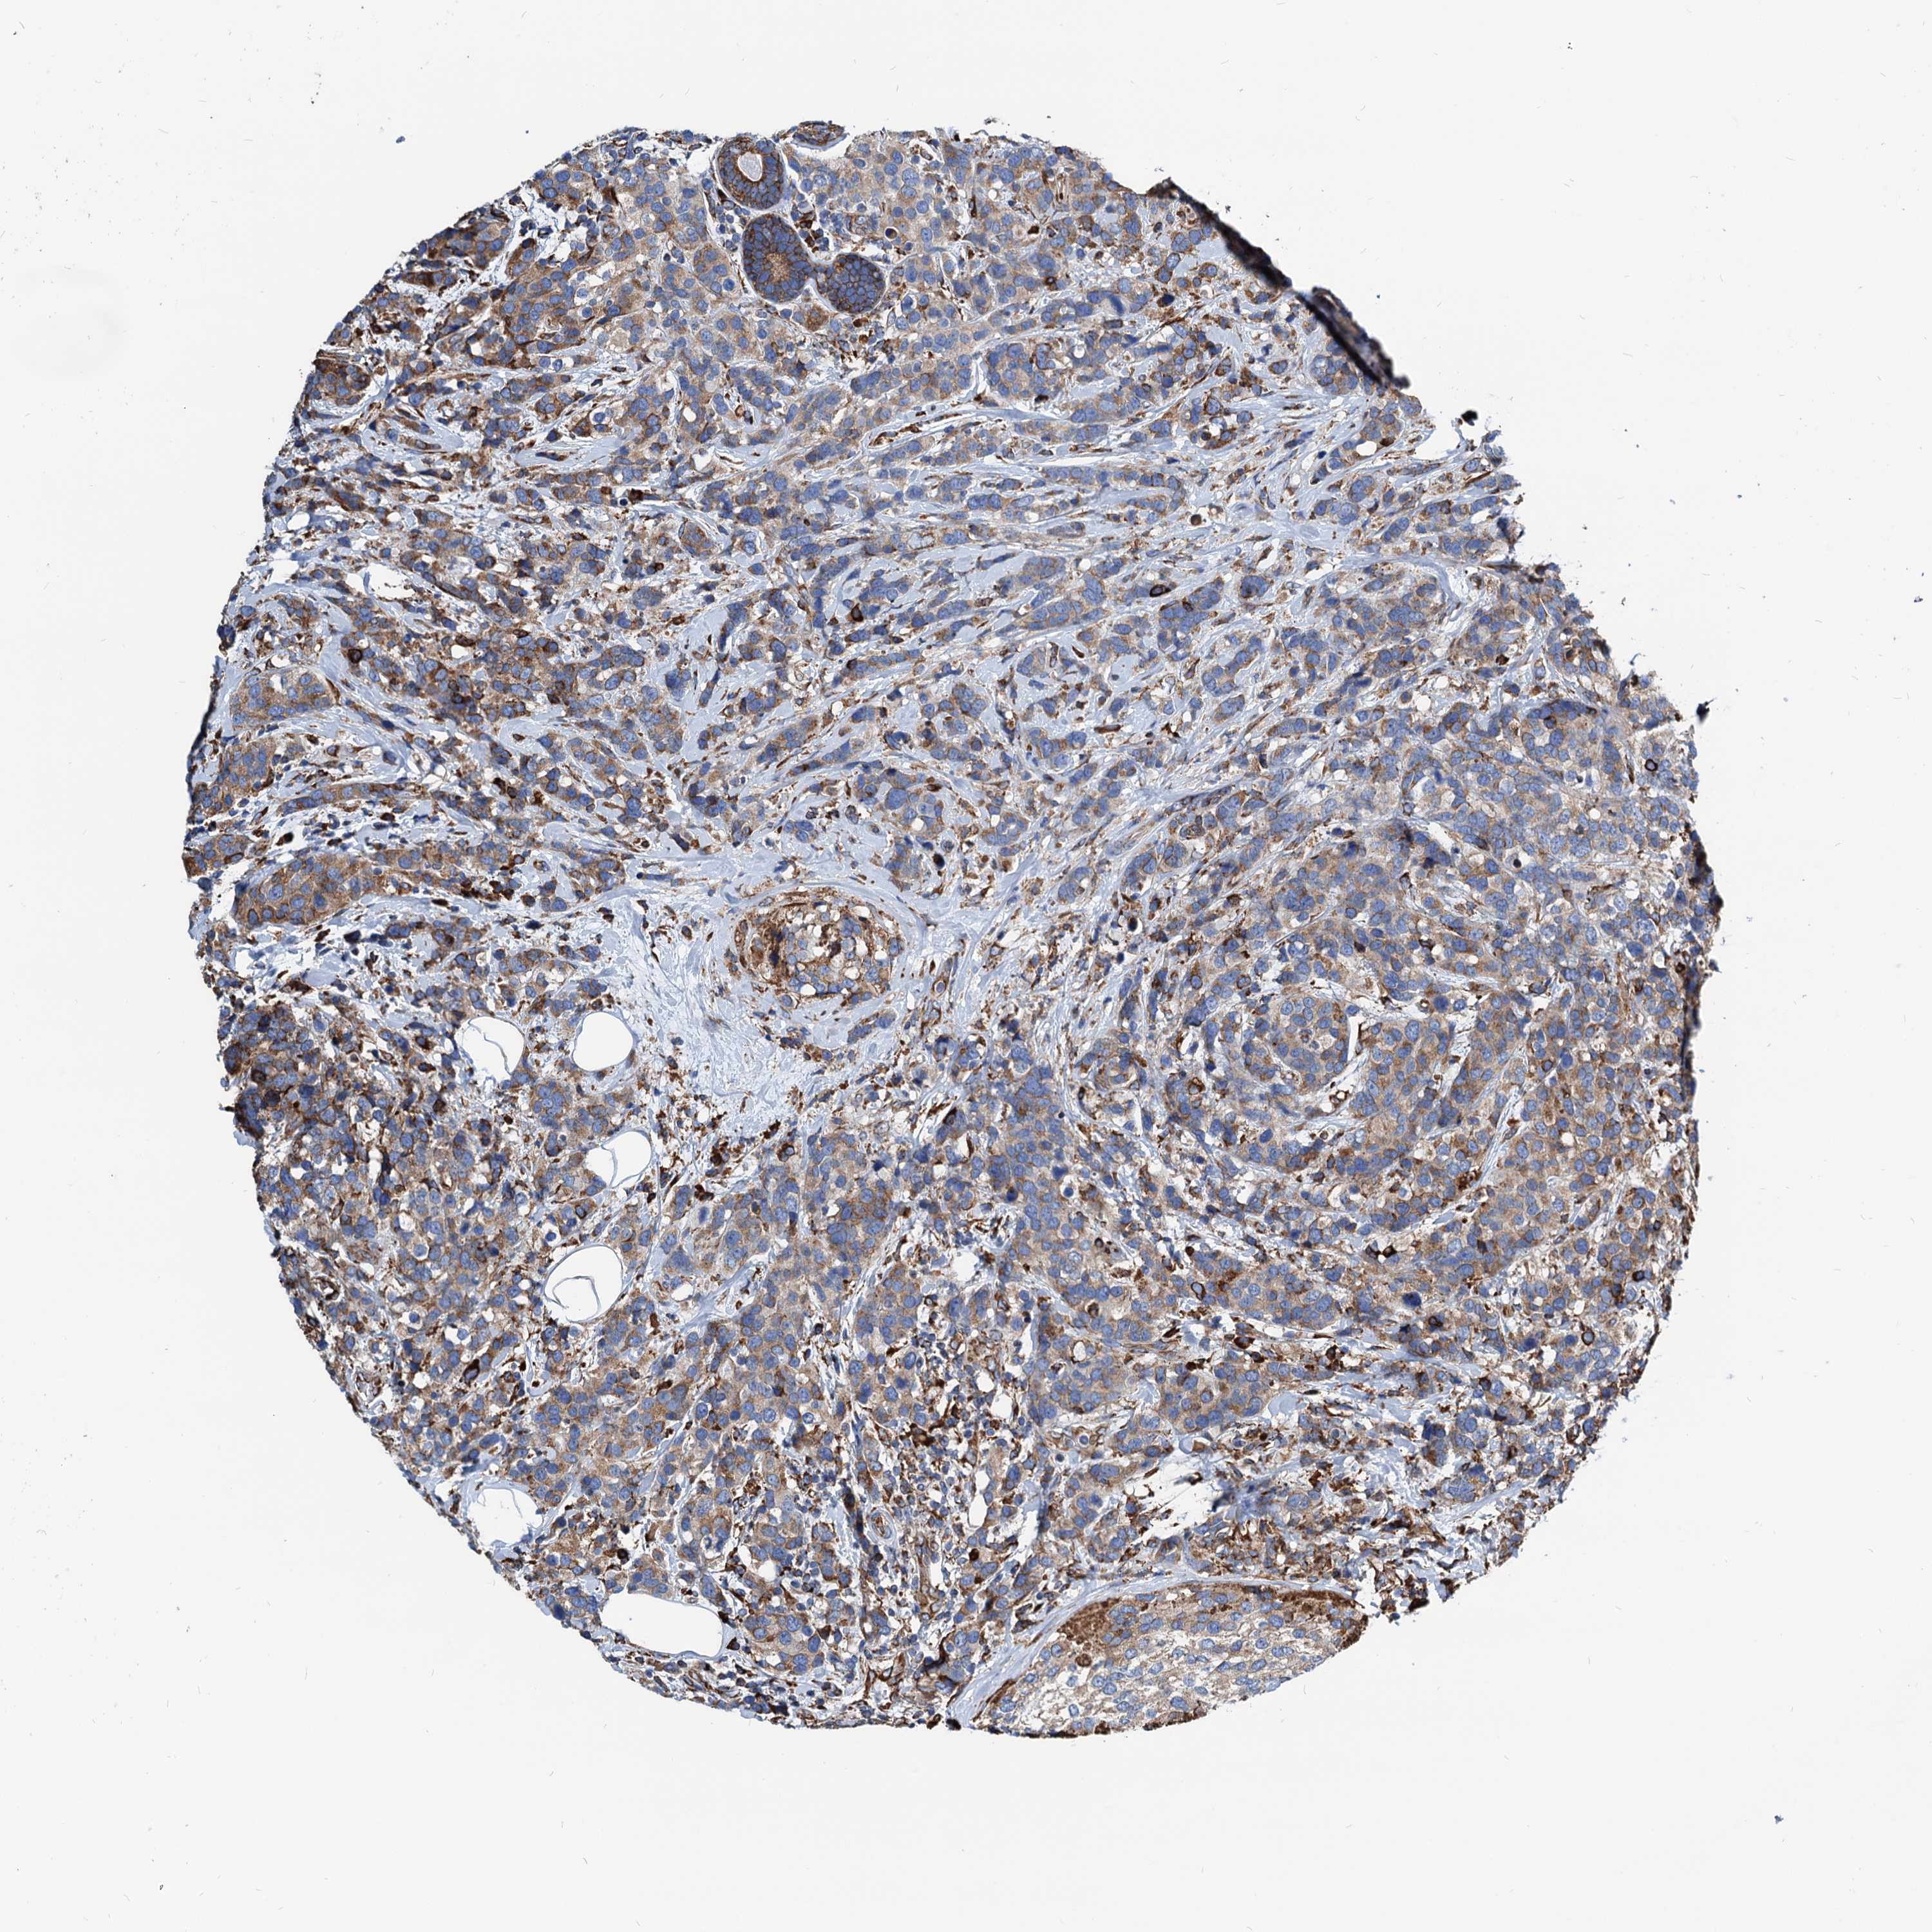

CANCER BREAST CANCER Show tissue menu

BRCA TCGA BRCA VALIDATION PROTEIN EXPRESSION

Breast cancer

Human cancer